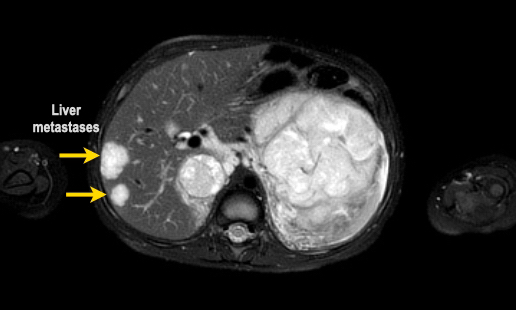

Hình ảnh

Hình ảnh MRI của một bé gái chín tháng tuổi có khối u ở bụng trái. MRI cho thấy khối u tuyến thượng thận trái, một phần đặc, một phần nang. Có nhiều di căn gan.

Khối u đã được sinh thiết. Có tình trạng chảy máu liên tục qua kim dẫn đường. Vào cuối thủ thuật, hai nút bọt gelatin đã được đặt vào (các dải tăng âm (mũi tên)).